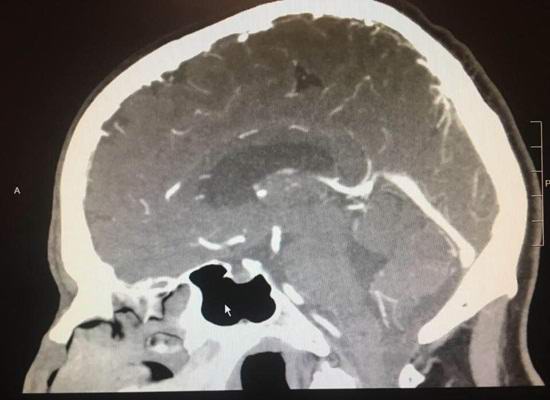

Lodaiin kaupungissa asuva Paul Wood alkoi valittaa päänsärkystä kipua muutama kuukausi sitten. Kun amerikkalainen kääntyi sairaalassa, hänelle todettiin aivokasvain. Määritetty riskialttiiksi leikkaus kuitenkin päivää aiemmin yhtäkkiä osoittautui, että kasvain vain kadonnut. Lääkärit eivät uskonneet silmiään milloin Röntgenkuva osoitti, että potilaan aivot palasivat terveeksi tilassa.

Asiantuntijat tunnustavat, että harvinaisissa tapauksissa pahanlaatuinen kasvain voi alkaa taantumasta yksinään asti täydellinen katoaminen. Kuitenkin jokaiselle materialistiselle huomioiden, tämä ei voi tapahtua yhdessä päivässä.